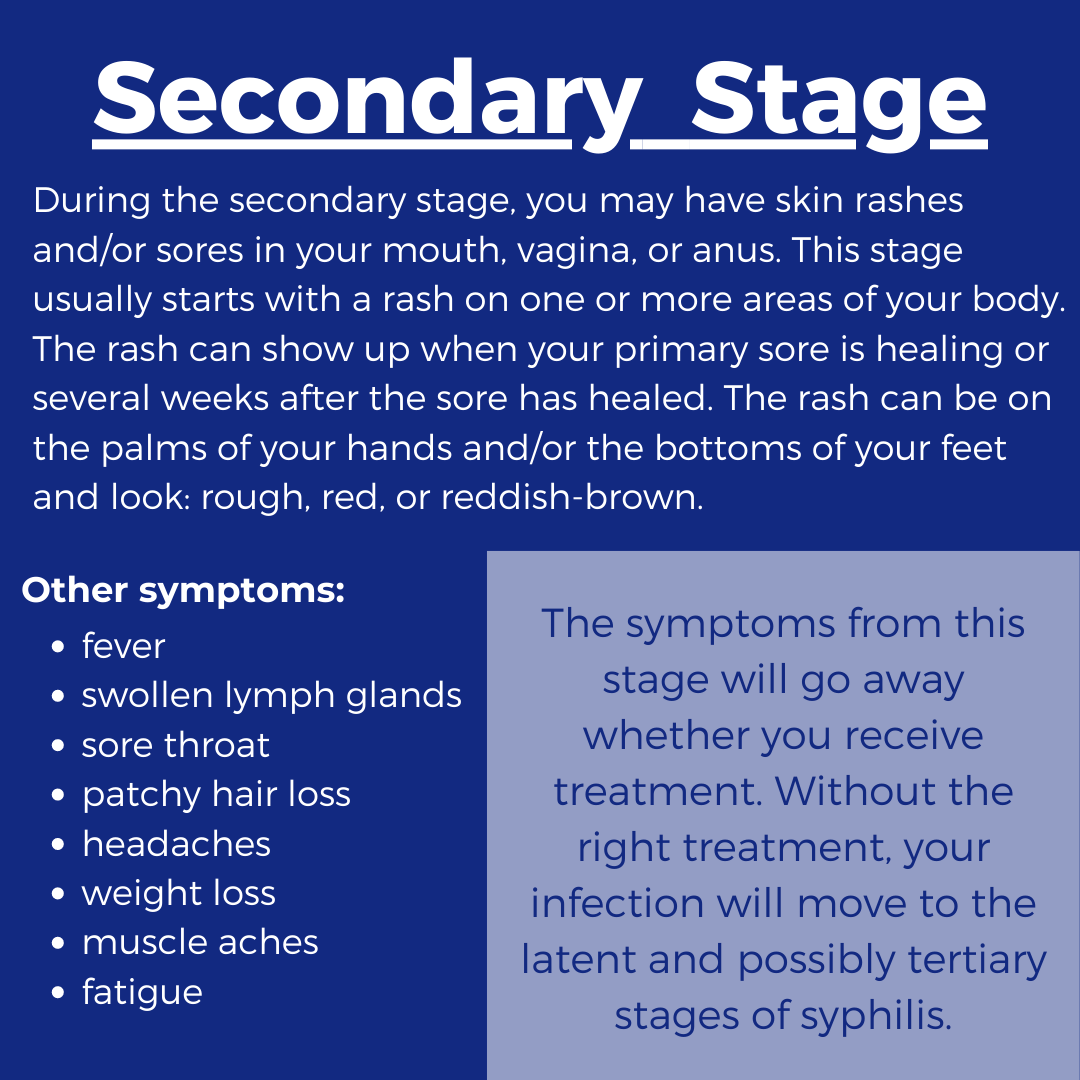

Stages of Syphilis: Symptoms, Causes, Prevention, and Treatment

Secondary Syphilis | Basicmedical Key

Syphilis – Symptoms | Risk Factors | Treatments | Prevention

Diphasic fever with generalised rash including palm and sole: secondary …

Signs and Symptoms – syphilis-the great imitator